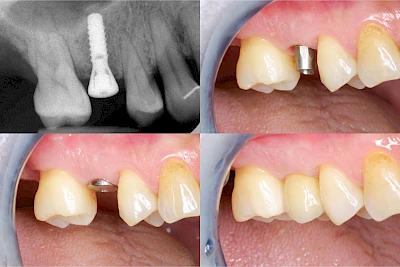

Fehlen einzelne Zähne und die Nachbarzähne sind unbeschadet oder gut zahnärztlich versorgt, werden immer häufiger Implantate gewählt, um die Lücken zu schließen. Auch bei größeren oder verteilten Lücken, wenn keine herausnehmbare Prothese gewünscht ist, werden Implantate für Kronen- bzw. Brückenversorgungen gesetzt. In Einzelfällen entscheiden sich sogar zahnlose Patienten für eine festsitzende Versorgung auf Implantaten.

Varianten zur Verankerung von festsitzendem Zahnersatz auf Implantaten